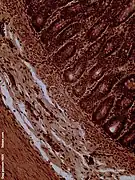

Histology

The jejunum contains very few Brunner's glands (found in the duodenum) or Peyer's patches (found in the ileum). However, there are a few jejunal lymph nodes suspended in its mesentery. The jejunum has many large circular folds in its submucosa called plicae circulares that increase the surface area for nutrient absorption. The plicae circulares are best developed in the jejunum.

- The villi of the jejunum look like long, finger-like projections, and are a histologically identifiable structure.

Dog jejunum (magnified 100-fold)